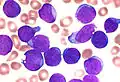

- Leukaemia, originate in the tissues responsible for producing new blood cells, most commonly in the bone marrow.

Carcinoma Leukaemia

The understanding of cancer was significantly advanced during the Renaissance period and in to the Age of Discovery. Sir Rudolf Virchow, a German biologist and politician, studied microscopic pathology, and linked his observations to illness. He is described as "the founder of cellular pathology".[13] In 1845, Virchow and John Hughes Bennett independently observed abnormal increase in white blood cells in patients. Virchow correctly identified the condition as blood disease, and named it leukämie in 1847 (later anglicised to leukemia).[14][15][16] In 1857, he was the first to describe a type of tumour called chordoma that originated from the clivus (at the base of the skull).[17][18]